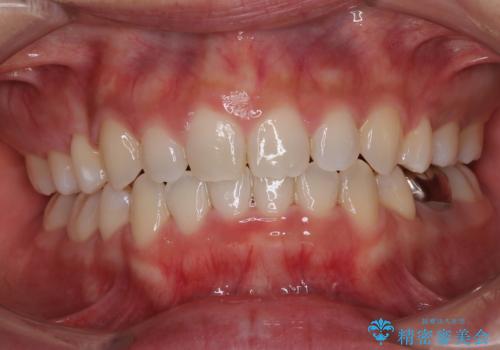

途中出産や育児があり、治療期間長くなってしまいましたが、ストレスなく唇が閉じられるような口元に仕上げることができました。

- 前歯のデコボコやクロスバイト、口元の突出感を気にして来院された患者様です。

上下左右の第一小臼歯4本を抜歯して、ワイヤー装置にて矯正治療を行うこととしました。